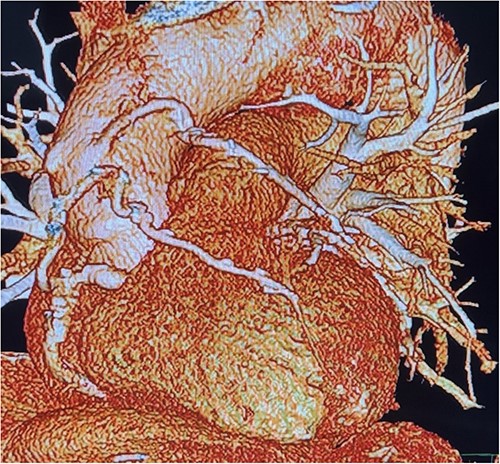

Before resternotomy, a cardiopulmonary bypass was performed via the right common femoral artery and vein. The RIMA was harvested in a semi-skeletonized fashion because skeletonized IMA is in general, longer than pedicled IMA. However, the RIMA could not reach the LAD in the present case due to cardiomegaly. Therefore, the proximal end of the RIMA was cut to use as a free graft. Subsequently, the proximal portion of the patent RA graft was tried to dissect as a proximal anastomosis site, but it was not possible due to severe adhesion of the surrounding tissue. Therefore, we decided to anastomose the proximal RIMA to the proximal right coronary artery (RCA) as the inflow site. The distal RIMA was anastomosed to the LAD as usual (Fig. 1). The postoperative course was uneventful, and the patient was discharged 11 days after the operation. A 3-month postoperative coronary angiogram showed the patency of the RA and RIMA conduits (Fig. 2). Moreover, from coronary computed tomography angiography after 6 years, it was confirmed that it was still patent (Fig. 3).

Post redoing coronary angiography showing patency of RIMA to LAD after 3 months.